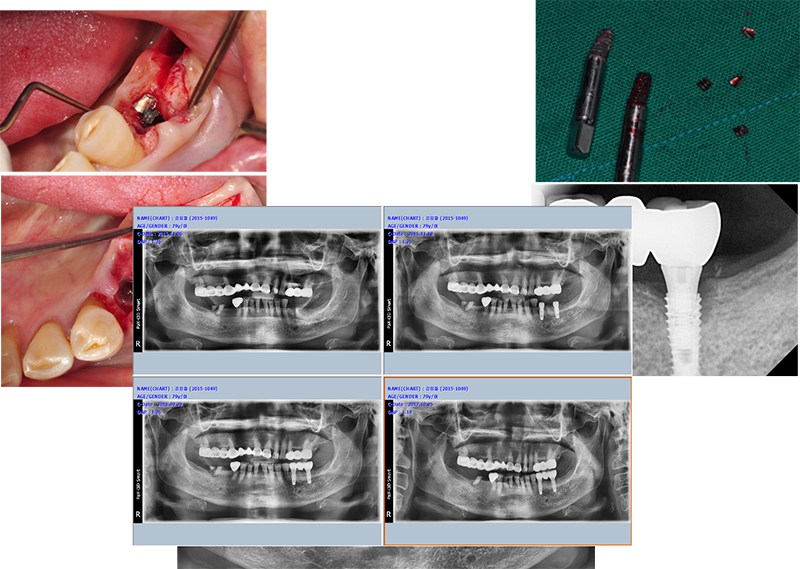

37¹ø 4.3 Á÷°æÀÇ ¿øÇöõÆ®

Á¦°ÅÇÏ´Ù°¡ ÈìÁýÀÌ ³¯ °Í °°¾Æ¼ Æ÷±âÇϰí

´ÙÀ½¿¡ ¾à¼Ó Àâ¾Ò´Âµ¥ ȯÀÚµµ Àúµµ ¹Ì·ç´Ù°¡ ÀÌ Áö°æµÊ.

ÆÄ³ë¶ó¸¶ »ó

°á±¹ ÇȽºÃÄ Á¦°Å

¾Æ¸¶µµ ±³ÇÕ¿¡ ¹®Á¦°¡ ÀÖ¾ú´ø µí

37¹ø abutment ÆÄÀý, µÚÂÊ¿¡ 8¹øÀÌ º¸À̰í, fixture Á÷°æÀÌ 5.0, Á¶±Ý ÈìÁýÀÌ ³ªµµ µÈ´Ù´Â »ý°¢À¸·Î Á¦°Å¼ö¼úÀ»

Çß´Ù.

3¹ø¿¡

³ª´²¼ °Ü¿ì Á¦°ÅÇÑ °æ¿ì